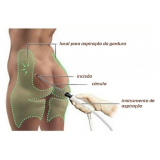

Lipoaspiração a Laser

Você merece a qualidade e comprometimento entregues pela equipe deste consultório médico e se neste momento está à procura de uma equipe que realize lipoaspiração a laser saiba que a FF Cirurgia Plástica disponibiliza de imediato este serviço para você!